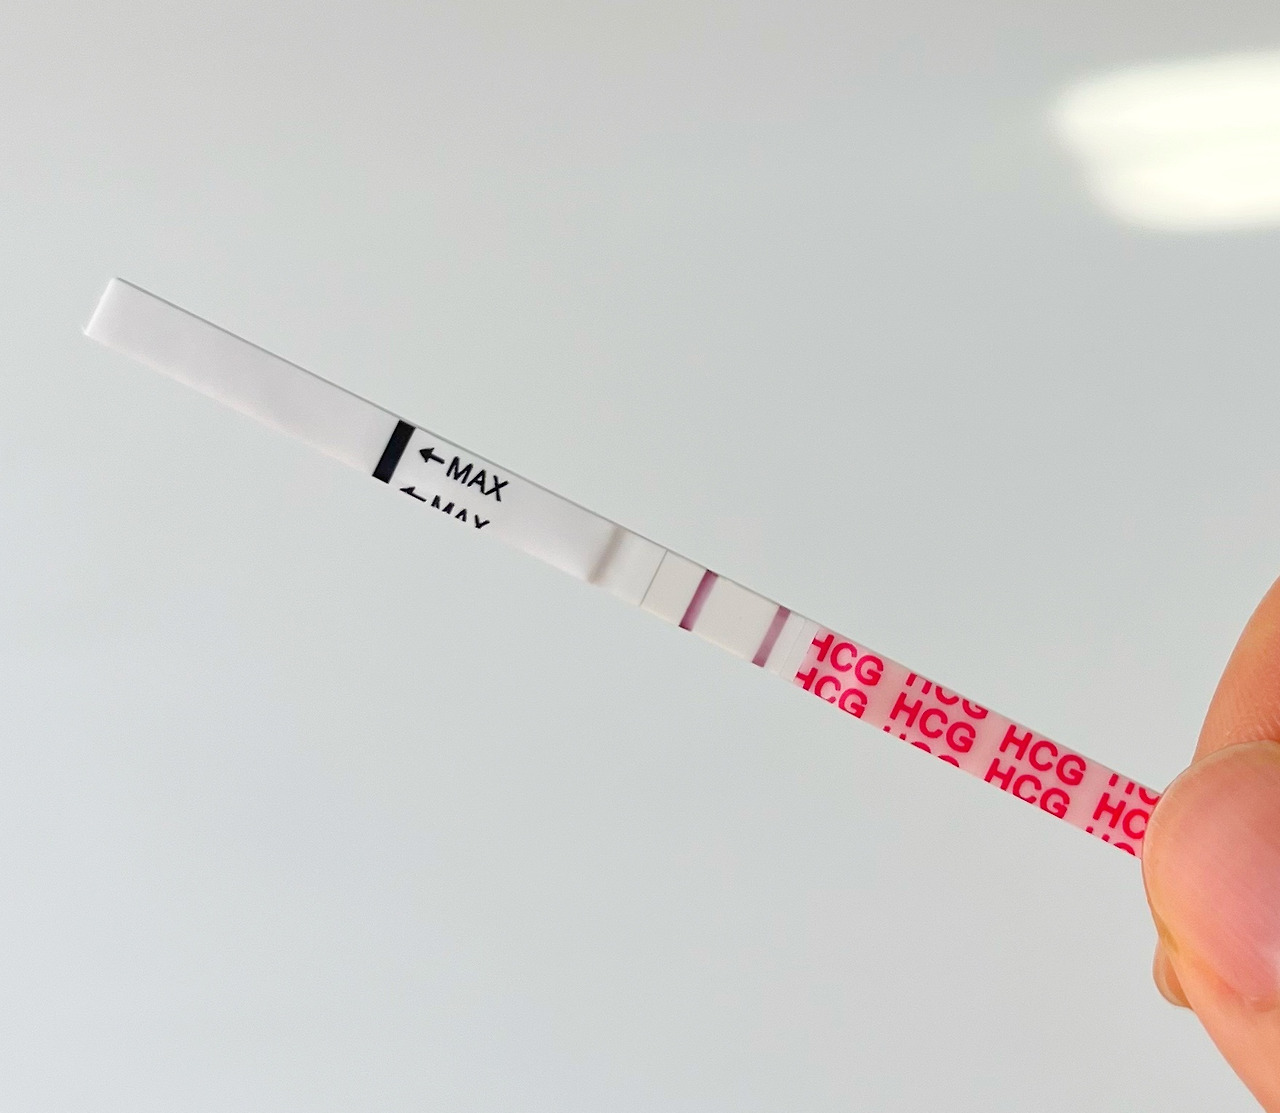

큰 기대 없이 배란 10일차 아침, 원포테스트기를 해보았다.

그런데, 엇...

신기하게 너무나 희미하게 내 눈에 정말 옅은 두 줄을 보게 되었다!!

나는 그동안의 무거웠던 머리가 순간 가벼워지면서 정말 희망을 본 기분이었다 :)

조금 어떨떨 하고 아직 임신인지 확신할 수 없어서 매일 오전 테스트기를 하나씩 했다.